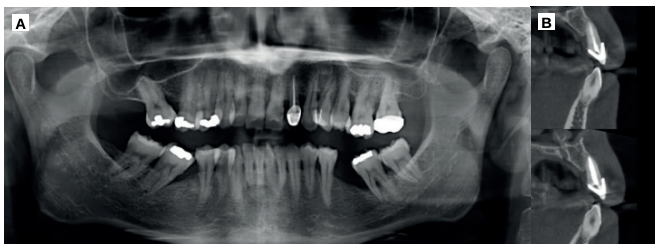

En la exploración radiográfica mediante radiografía panorámica se apreciaron los molares inferiores mesializados por la ausencia de los primeros molares inferiores (Figura 4A). En el escáner de haz cónico se evaluó el nivel de inserción del incisivo lateral superior izquierdo (Figura 4B).

verticales en zonas de molares. (B) Escáner de haz cónico, donde se aprecia el soporte óseo reducido del incisivo lateral

superior izquierdo.